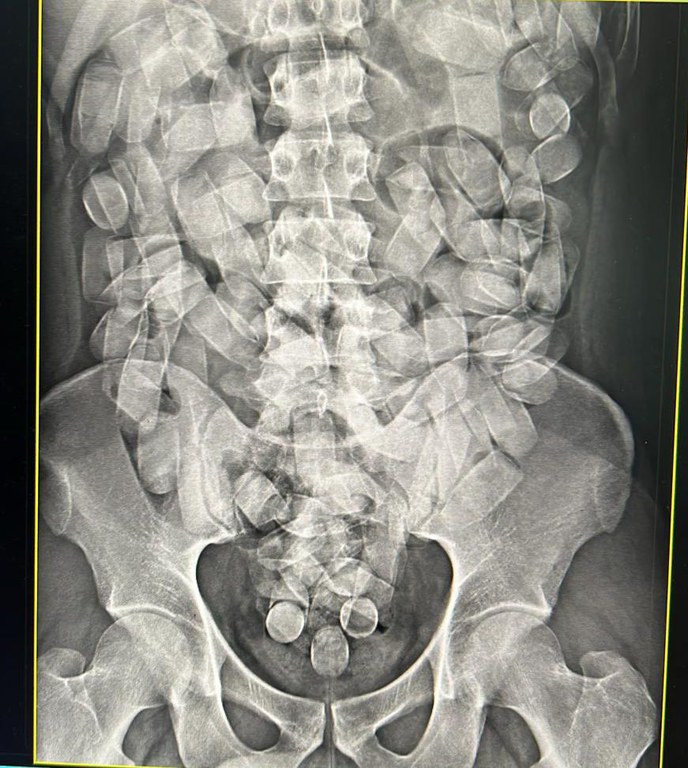

O passageiro transportava cápsulas de cocaína no estômago.

Corumbá/MS. Neste domingo, 19/05, policiais federais realizaram a prisão em flagrante de um homem quando tentava embarcar no aeroporto de Corumbá/MS transportando cocaína, em cápsulas, em seu estômago.

O passageiro, que tinha por destino São Paulo, transportava 125 cápsulas ingeridas de cocaína.